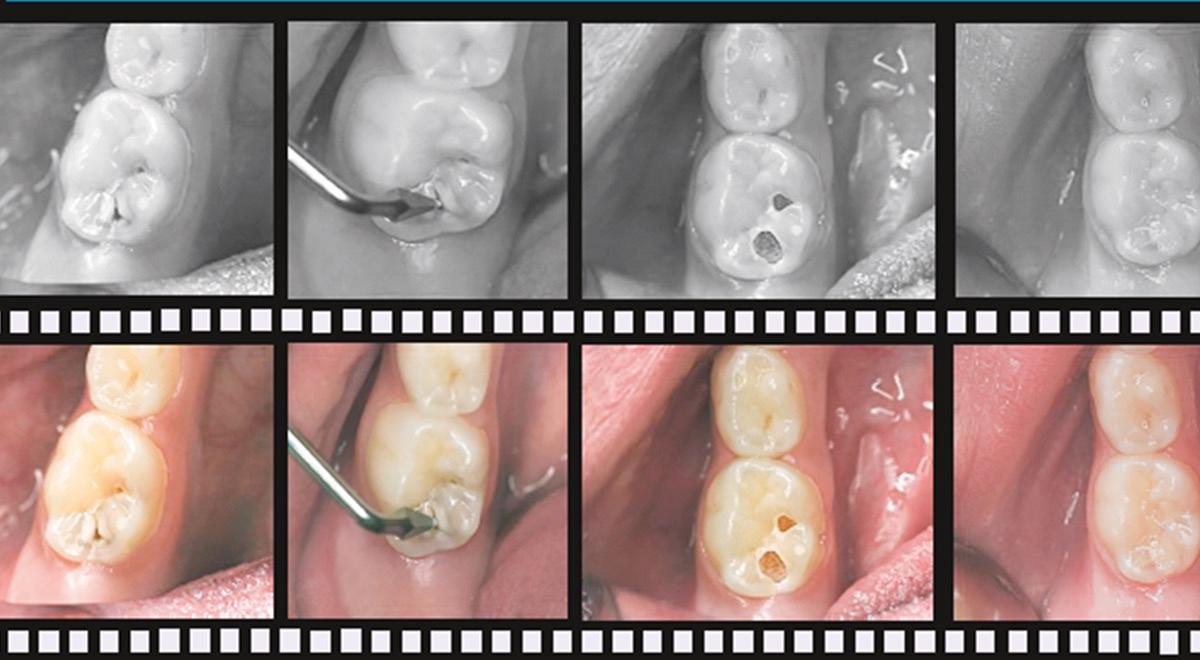

De Atraumatic Restorative Treatment (ART) ontstond in Tanzania uit noodzaak, maar groeide uit tot een wereldwijd toegepaste weefselsparende behandelmethode. In gebieden zonder toegang tot elektrische apparatuur en amalgaam bood ART een oplossing: met handexcavatoren wordt geïnfecteerd dentine verwijderd, waarna een glasionomeercement wordt aangebracht. Deze eenvoudige maar effectieve techniek bleek breed toepasbaar, ook buiten lage-inkomenslanden, bijvoorbeeld in de jeugd- en ouderenzorg. In deze nascholing maakt u kennis met de achtergrond en ontwikkeling van ART, onderbouwd met bevindingen uit 503 wetenschappelijke publicaties. De opbouw volgt de inhoud van het naslagwerk: van de principes van weefselsparende tandheelkunde en het gebruik van handinstrumenten (hoofdstukken 2–3), tot de materiaaleigenschappen van glasionomeer en de toepassing van ART-verzegelingen en -restauraties (hoofdstukken 4–9). ART biedt tandartsen wereldwijd een laagdrempelige methode om angstige patiënten te behandelen en restauratieve zorg toegankelijk te maken. Deze e-learning reikt u de kennis en vaardigheden aan om ART verantwoord en effectief toe te passen.